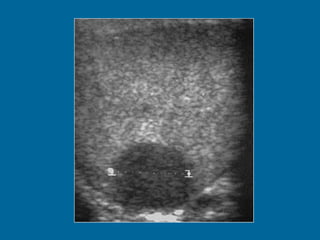

C A R C I N O M A  D E  C E L U L A S  E M B R I O N A R I A S Generalidades  Segunda neoplasia germinal más frecuente. Pico de incidencia entre la segunda y tercera década de vida. A menudo mixto. Mayor agresividad que el seminoma. Poco quimio y radiosensibles con altos niveles de AFP. Forma infantil, tumor del seno endodérmico o saco vitelino.

Ecografía Masa o nódulo Pequeño. Ecoestructura heterogénea. Hipoecogénico. Márgenes mal delimitados. Degeneración quística. Focos ecogénicos con o sin sombra acústica.

C A RC I N O M A D E C E L U L A S E M B R I O N A R I A S Generalidades Segunda neoplasia germinal más frecuente. Pico de incidencia entre la segunda y tercera década de vida. A menudo mixto. Mayor agresividad que el seminoma. Poco quimio y radiosensibles con altos niveles de AFP. Forma infantil, tumor del seno endodérmico o saco vitelino.

Ecografía Masa onódulo Pequeño. Ecoestructura heterogénea. Hipoecogénico. Márgenes mal delimitados. Degeneración quística. Focos ecogénicos con o sin sombra acústica.